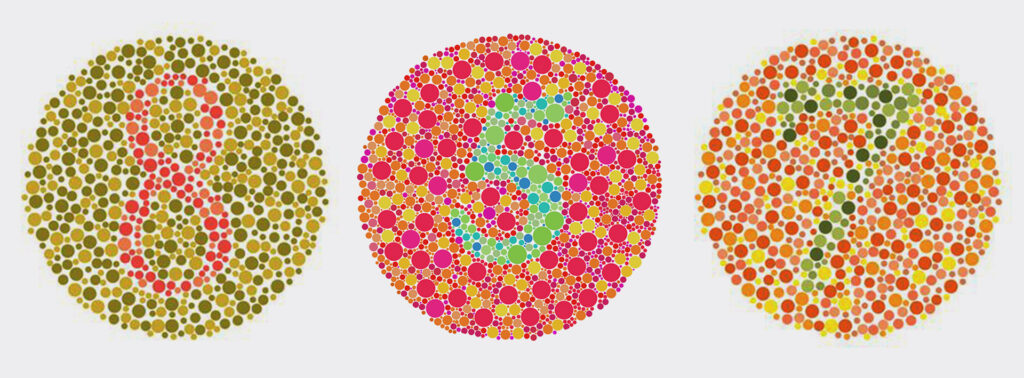

Diagnosis is carried out quickly in the doctor's office with the use of special colour charts Ishihara.

The patient is asked to identify numbers formed by colour spots, allowing the ophthalmologist to determine the type and severity of the dyschromatopsia.

Very often! Children learn to name colours from memory (e.g. they know that grass is “green” even if they see it as yellow). Diagnosis is usually made in preschool with the Ishihara test.